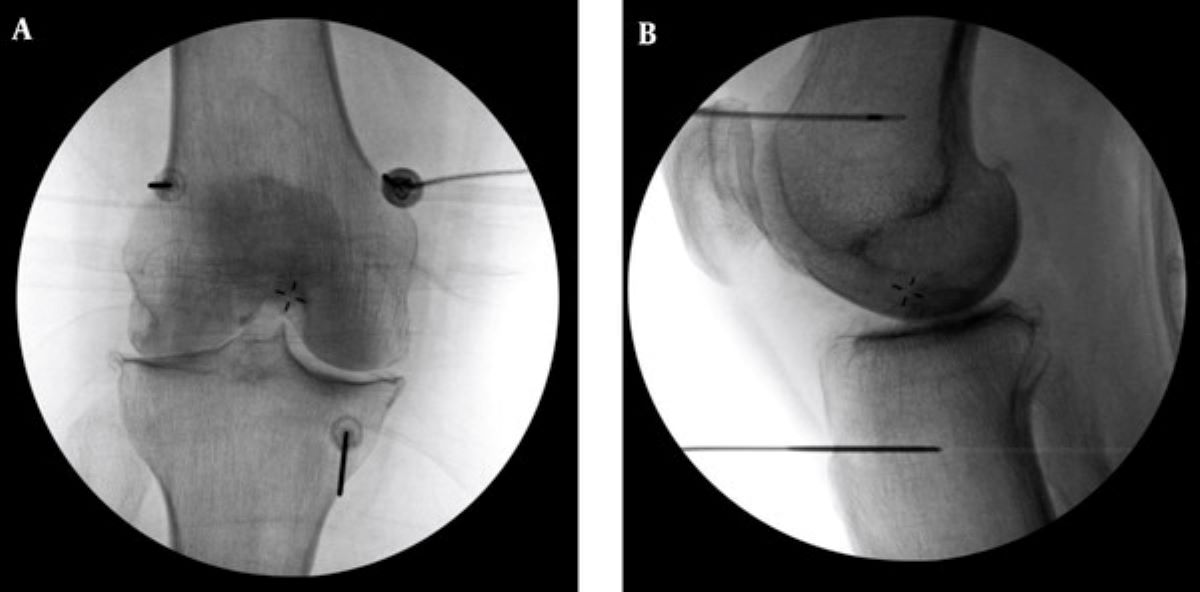

診斷上,退化性關節炎可透過X光查看軟骨縫隙、有無骨刺等,結合身體檢查觀察關節的穩定度、疼痛情況以及是否積水,藉此評估退化程度。原則上,中度以前多能藉由藥物、復健、肌力訓練、生活調整與體重控制改善,中晚期的患者則可能需要置換人工關節,但針對不適合手術或不願手術的患者,則可採用「高頻熱凝療法」止痛。李宜軒醫師說明:「此項技術過往多用於椎間盤突出、滑脫等脊椎神經壓迫造成的下背痛、坐骨神經痛的止痛治療,近來也運用至膝關節退化。執行方式是在局部麻醉的情況下,以X光定位將電極導針導引至膝蓋的三個主要感覺神經叢,確認施行目標後,接上電源線輸出高頻電波,藉由熱能與電效應,使引起疼痛的神經失去傳導疼痛的能力,降低疼痛。」為確保施行過程中未傷及運動神經,治療前會進行不同電量測試,並請病人活動膝蓋,在確定不影響日後活動的情況下進行治療。一般而言,效果會在術後當下至一週內顯現,普遍可維持半年至一到兩年,因人而異。但若有急性感染、心律調節器或正在服用抗凝血劑者即不適用此治療,需由醫師進行評估。

圖說:高頻熱凝療法以X光定位將電極導針導引至膝蓋的三個主要感覺神經叢,藉由熱能與電效應,麻痺痛覺神經。(圖片提供:台北慈濟醫院)